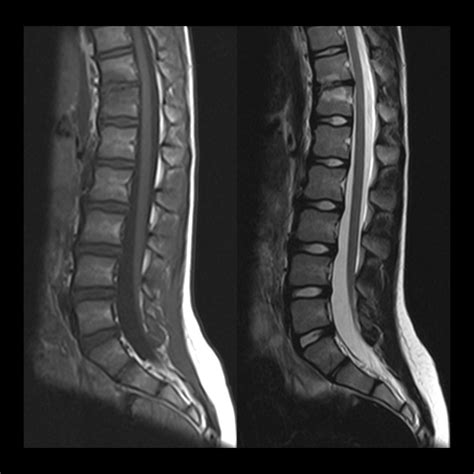

Tethered Cord MRI plays a pivotal role in the diagnosis of tethered cord syndrome. This imaging technique uses magnetic fields and radio waves to produce detailed images of the spinal cord and surrounding structures. Unlike traditional MRI, Tethered Cord MRI focuses specifically on the spinal cord, providing high-resolution images that can detect even the slightest abnormalities.

One of the key advantages of Tethered Cord MRI is its ability to visualize the spinal cord in multiple planes. This allows radiologists to get a comprehensive view of the spinal cord and identify any areas where it may be tethered. The images obtained from Tethered Cord MRI are also highly detailed, making it easier to pinpoint the exact location and extent of the tethering.

After the Tethered Cord MRI procedure, the images will be reviewed by a radiologist who specializes in interpreting MRI scans. The radiologist will look for signs of tethered cord syndrome, such as:

• Abnormal Attachments: The spinal cord may be attached to surrounding tissues, such as the dura mater or vertebrae, in an abnormal manner.

• Thickened Filum Terminale: The filum terminale is a thin, fibrous structure that anchors the spinal cord. In tethered cord syndrome, this structure may be thickened or shortened.

• Spinal Cord Stretching: The spinal cord may appear stretched or elongated, indicating that it is being pulled down by the tethering.